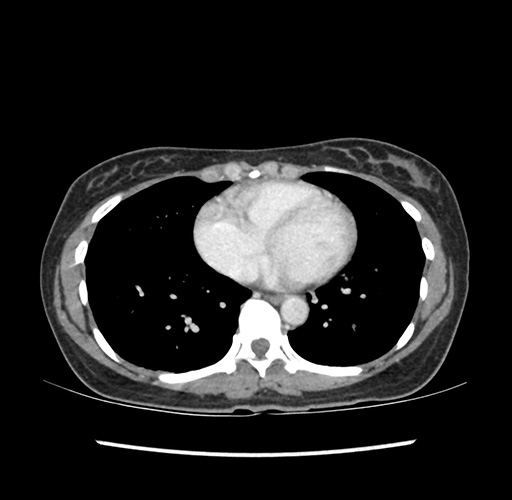

Imaging Analysis

Look through the patient's CT scan to identify any areas of concern for the necessary procedure.

Based on your CT findings, which issue(s) would give reason for "planned slowing down moment(s)" in this case?